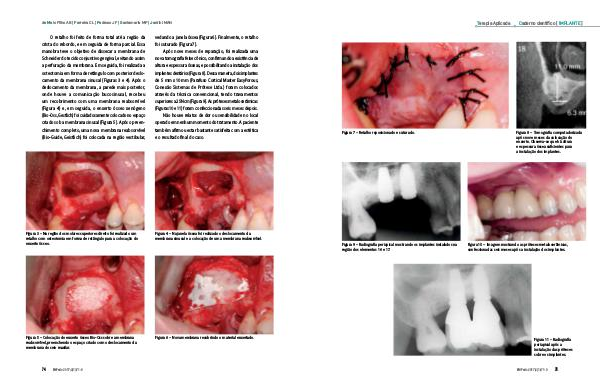

Terapia Aplicada Figura 7 – Retalho reposicionado e suturado. Figura 9 – Radiografia periapical mostrando os implantes instalados na região dos elementos 16 e 17. Caderno científico [ IMPLANTE ] Figura 8 – Tomografia computadorizada após nove meses da colocação do enxerto. Observa-se que há altura e espessura óssea suficientes para a instalação dos implantes. Figura 10 – Imagem mostrando as próteses metalocerâmicas, confeccionadas seis meses após a instalação dos implantes. Figura 11 – Radiografia periapical após a instalação das próteses sobre os implantes. INPerio 2017;2(1):71-8 75